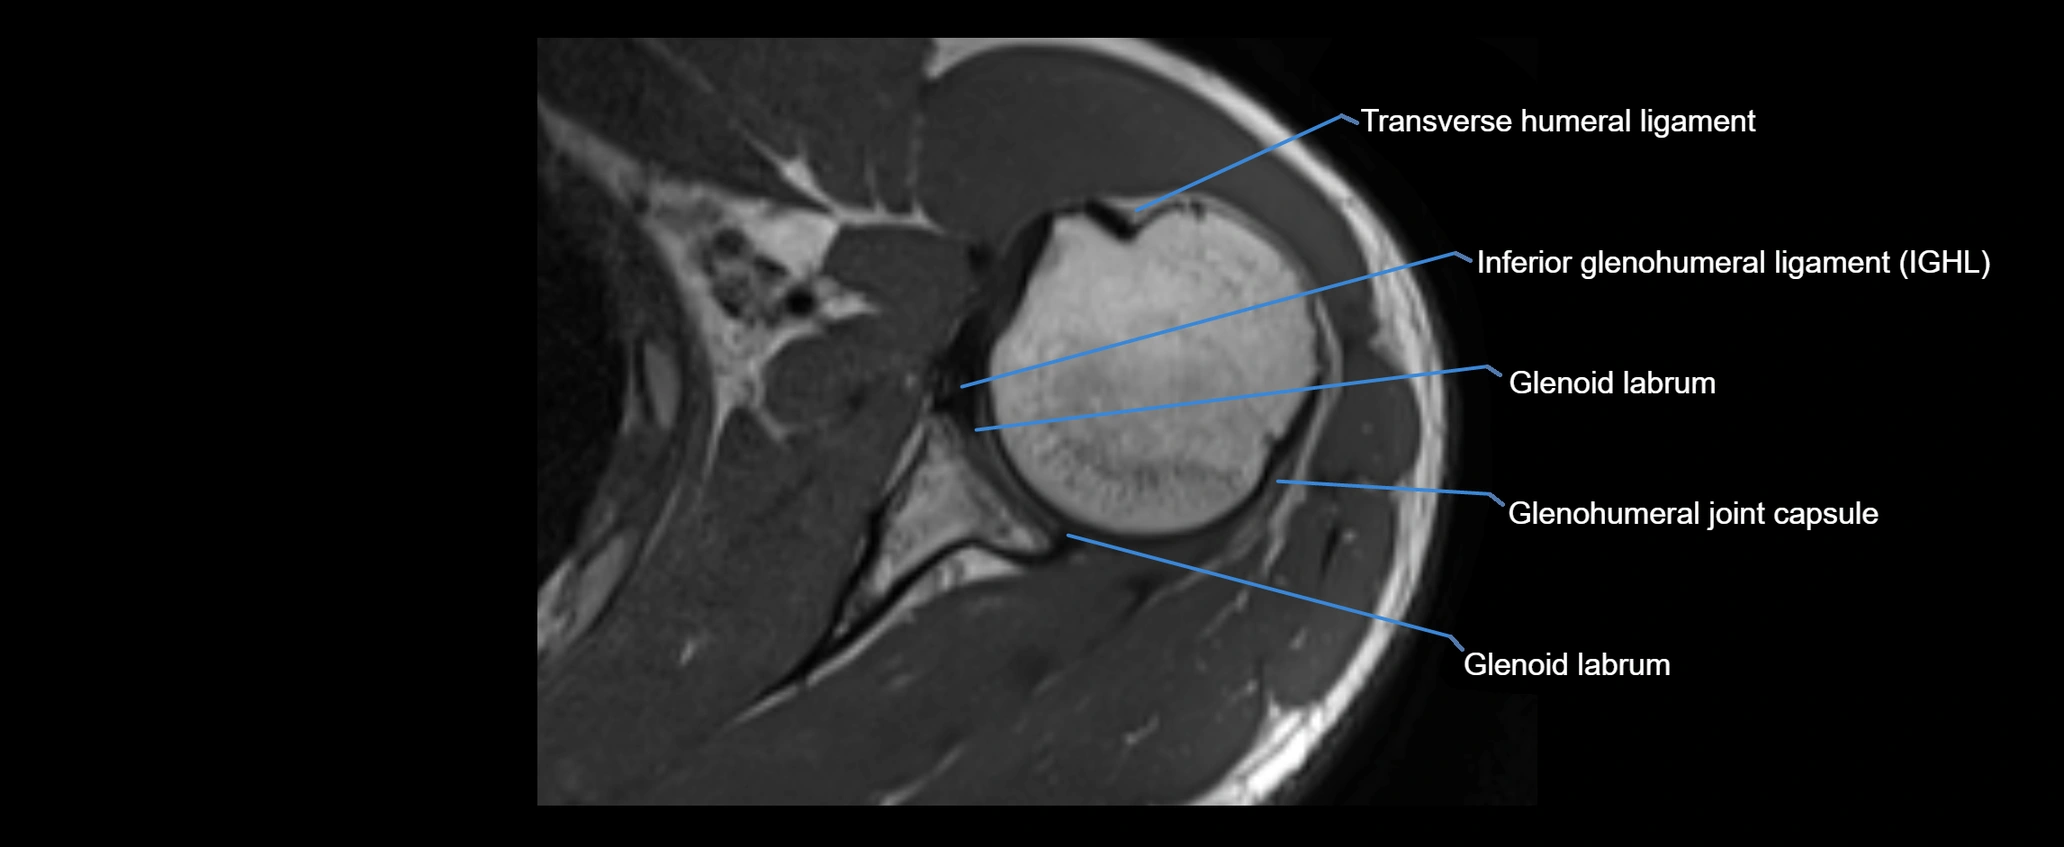

CT image

image